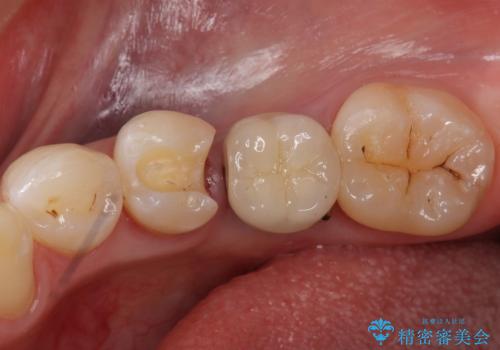

- 下の奥の銀歯を白くしたいとのことで来院されました。

セラミックインレーでの治療を行いました。

銀の詰め物のやり替えは2回の来院で終わらせることができます。

下の歯は口を開けたときに外からよく見えるため、セラミックにやり替えることで印象が大きく変わります。